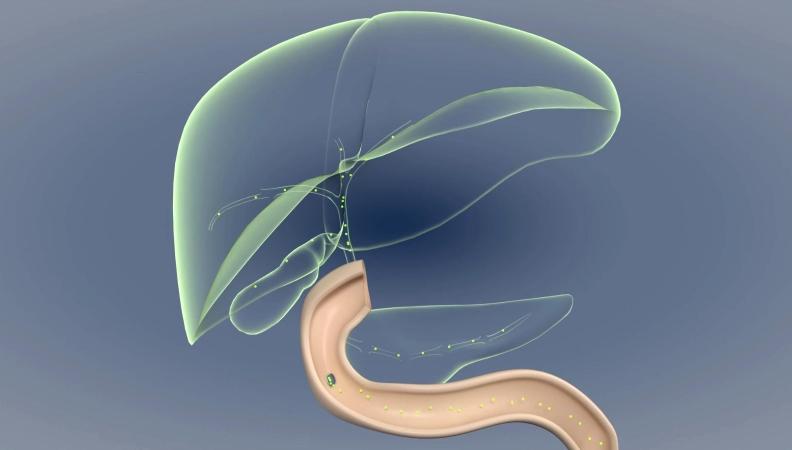

科技新突破丨我国科学家揭示胆汁淤积瘙痒的分子机制